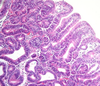

grade this disease

what does micro show?

low grade dysplasia of Barrett esophagus

crowded hyperchromatic nuclei

decreased goblet cell formation

grade this disease

what is found in micro

low grade dysplasia of Barrett’s esophagus

loss of cell polarity, but nuclei still mostly basal

some gland architectural irregularity => mostly not branched or back-to-back